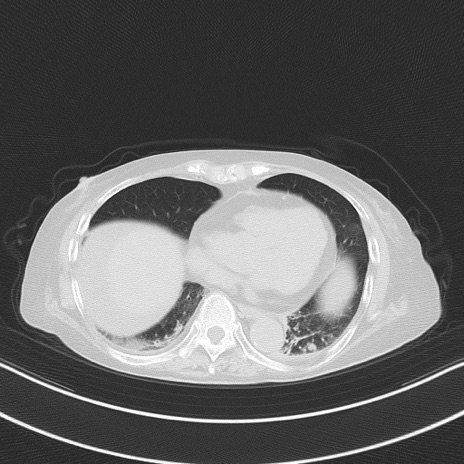

横断像

冠状断像